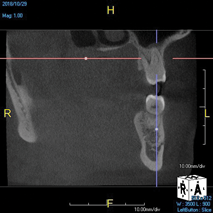

(10.) Tooth No. 31 in this 14-year-old patient does not exhibit caries. It is a “ghost tooth.” The lack of a periapical pathosis, the location of the tooth relative to the inferior alveolar nerve, and the development of tooth No. 32 are all visible in the CBCT image. These factors will aid the clinicians in developing a treatment plan to deal with this unusual internal resorption case.

Figure 10